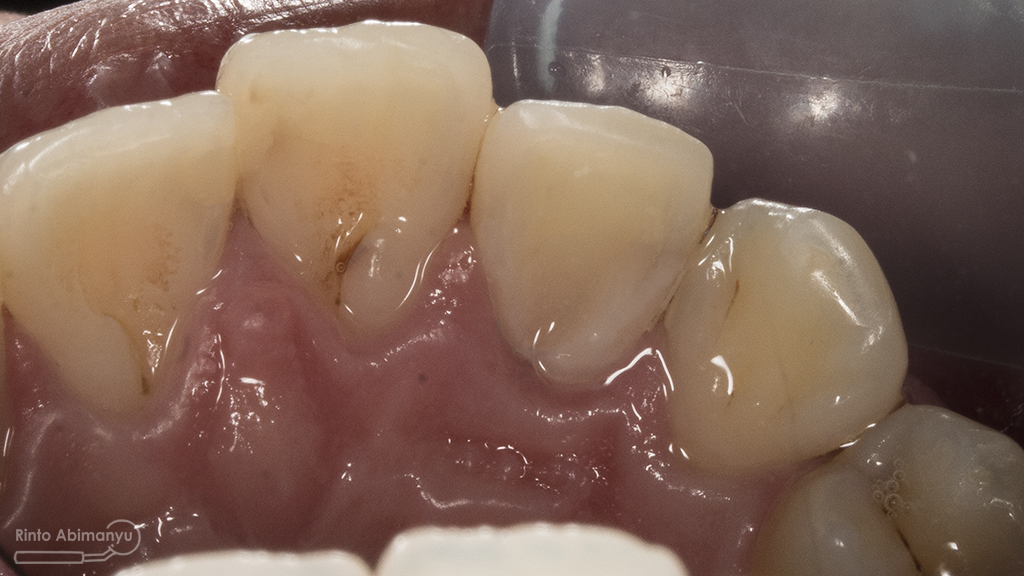

ini hasil preparasi gigi-giginya…

Hasil preparasi tampak depan

Hasil preparasi tampak oklusal